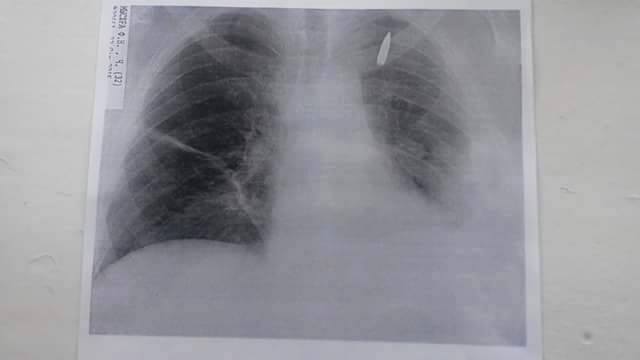

UPD (13.02.2015) Бійцю зробили надскладну операцію у Вінницькому госпіталі . Видалили кулю, яка мігрувала і щосекунди могла обірвати життя чоловіка. Кулю видалили разом зі шматком легені. Федір бореться. Заради дружини, заради донечки, заради нас з вами і нашої віри в хороше. Бореться, щоб вчергове не вбивати нашу надію. Давайте допоможемо Федору боротись.